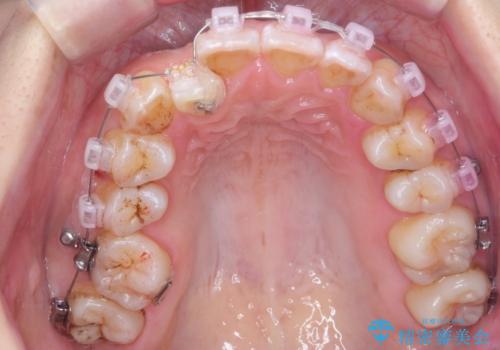

上の歯列を後ろに下げるのに、矯正用ミニスクリューを使用しています(インプラント矯正)

下については、まずは動かして起こしてみて抜歯の本数は治療をすすめながら1本、右上下2本、上下左右4本の選択肢のうちどれかになるという方針としました。

初めから抜歯をしてしまうと戻れない為です。